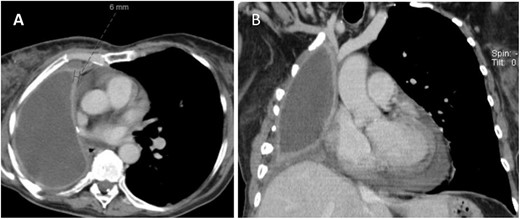

A 60-year-old woman with stage IIIA right lung adenocarcinoma underwent neoadjuvant chemoradiation followed by pneumonectomy. Nine years later, surveillance CT/PET scans revealed new right pleural thickening and nodular avidity with concerns for malignant recurrence (Figs 1 and 2). Her only symptom was chronic chest pain attributed to post-thoracotomy syndrome. She had no respiratory symptoms. She underwent a bronchoscopy which showed an intact right mainstem bronchial stump without signs of tumor or fistula. Upon entry into the pleural cavity during video-assisted thoracoscopic surgery for pleural biopsy (VATS), 10 mL of white, non-odorous fluid was drained. There was no intra-operative suggestion of cancer recurrence. Pathology of the pleural biopsy showed acute inflammation with underlying chronic pleuritis and no tumor. Pleural cultures were positive for N. nova, consistent with PPE (Fig. 3). She then started on intravenous trimethoprim-sulfamethoxazole and amikacin. Brain MRI and blood cultures were negative for disseminated nocardiosis. She was planned for washout and muscle transposition to fill the pneumonectomy space, but clinically deteriorated after aspiration pneumonia and cardiogenic pulmonary edema. She elected for comfort measures and expired shortly afterwards.

CT (A) axial and (B) coronal views showing fluid filled pneumonectomy space with nodularity and thickened right pleura measuring 6 mm anteriorly.